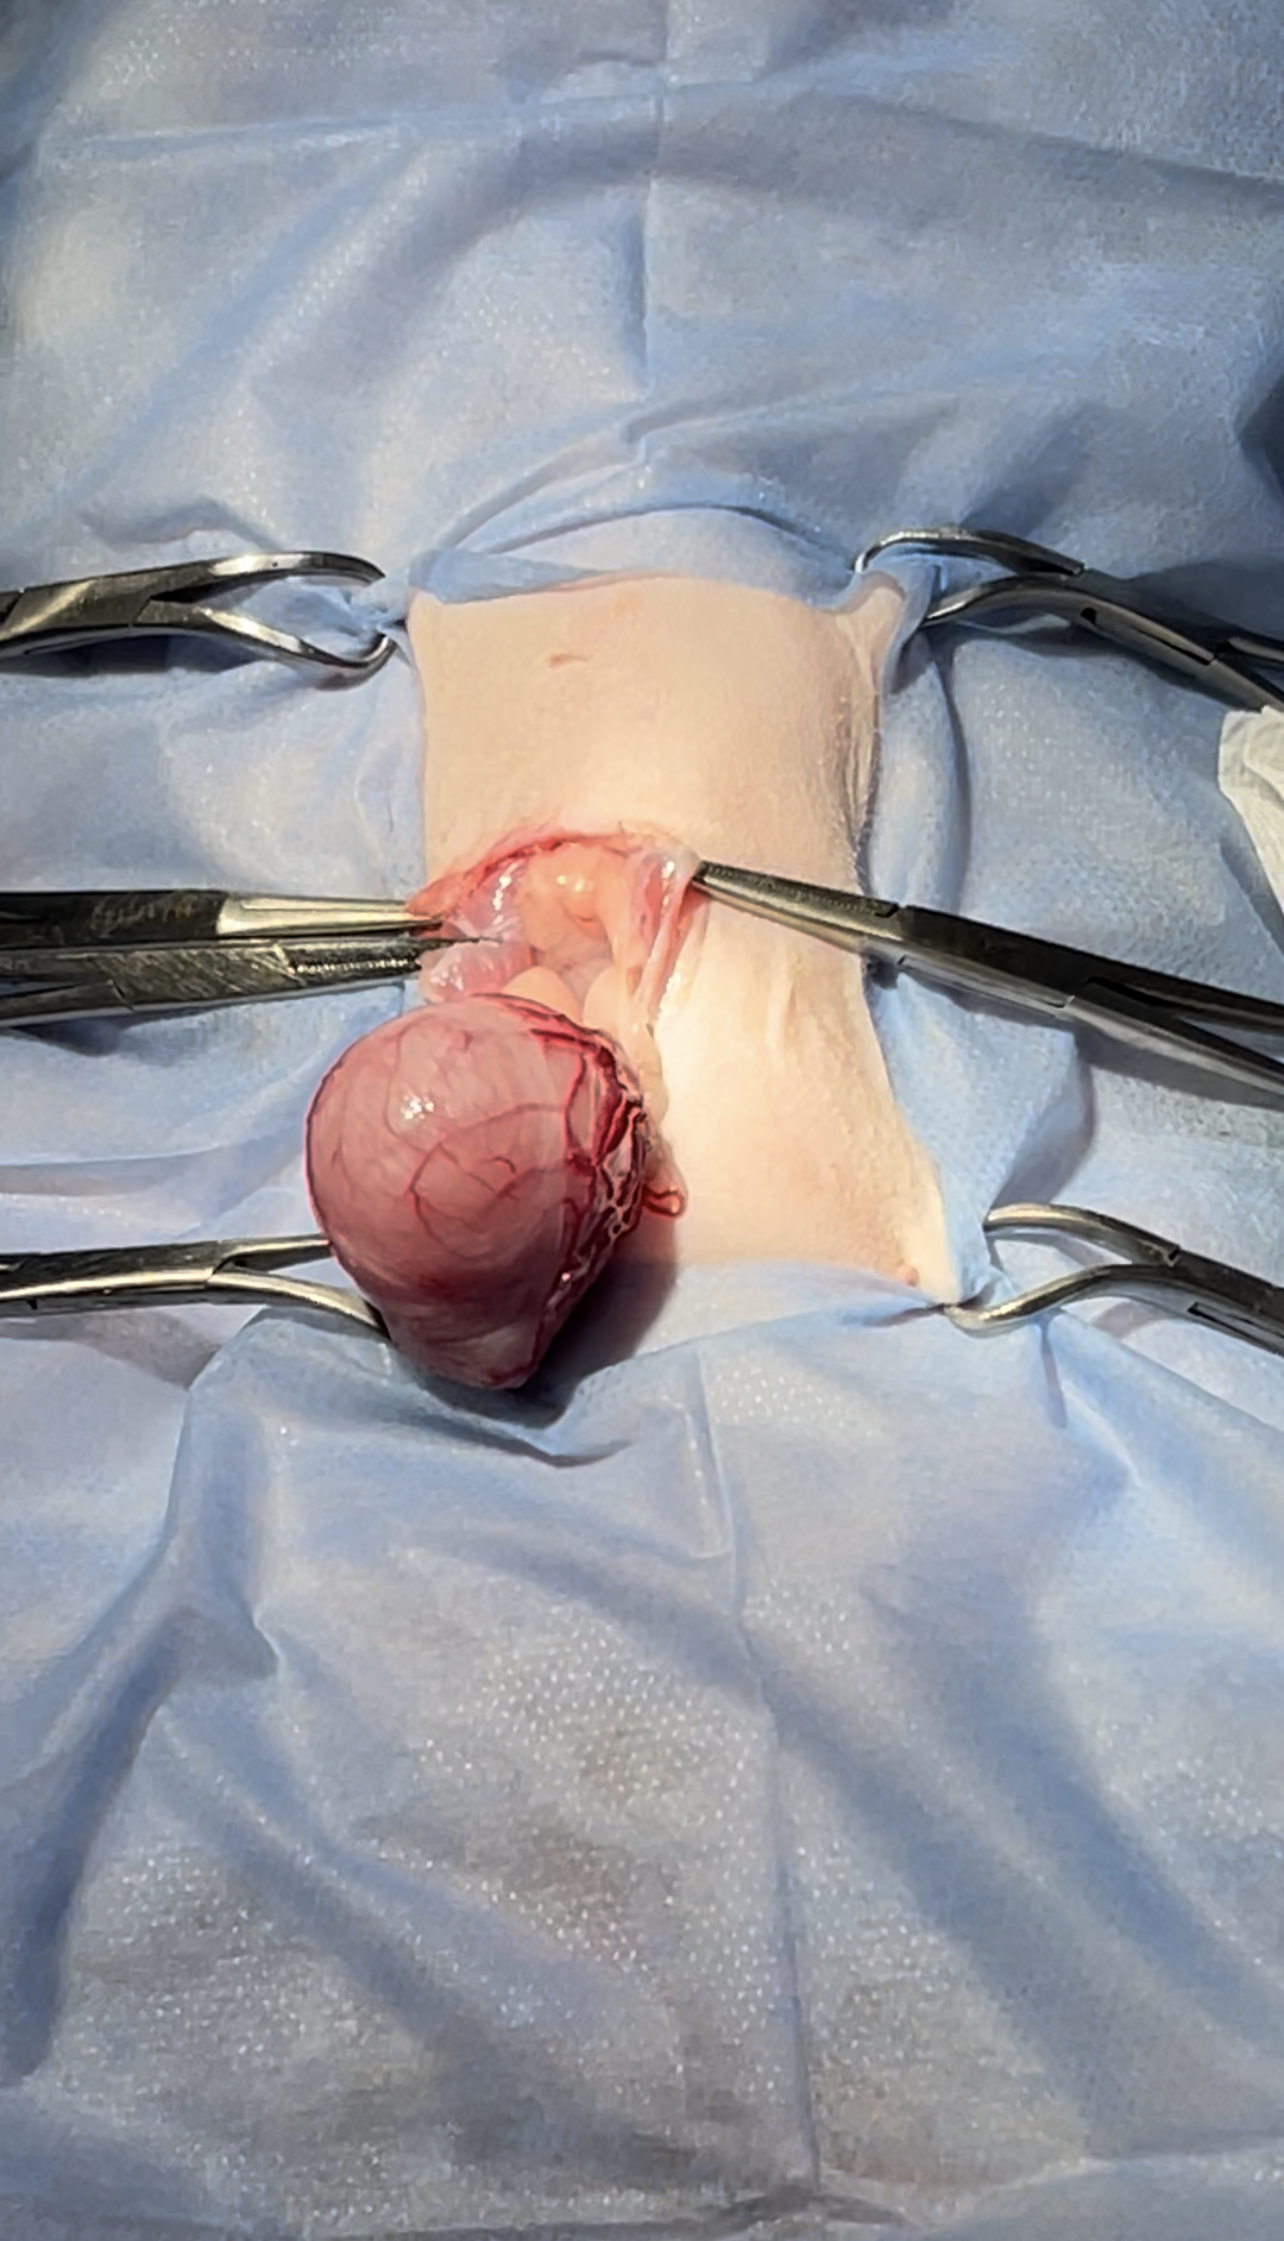

One large bladder stone

Ventral Midline approach extending from the umbilicus to the pelvis

Bladder is then exteriorized

Isolation to prevent any un wanted contamination

Stapp incision the the ventral part

bladder is visualized

Removal of the stone

Stone removed measuring 3 cm